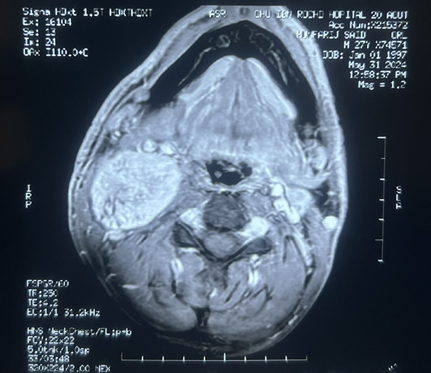

Magnetic resonance imaging (MRI)

of the neck confirmed a 39x38x60 mm properly limited mass with high signal

intensity on T1-weighted MRI and a heterogeneous, low signal intensity on T2

weighted MRI (Figure 1). After

intravenous administration of gadolinium-based contrast material, the lesion

showed irregular peripheral enhancement. Carotid artery angiography was

performed because of the close relationship between the mass and the carotid

artery. The angiography showed a normal filling in the right common, internal,

and external carotid arteries and their branches. (Figure 2).

Figure 2: Coronal (A) sagittal (B) and axial(C) view. Gray

arrow: well-circumscribed, h mass with dimensions of 39x38x60 mm in the right

lateral cervical region directly under the right sternocleidomastoid muscle,

separating the internal jugular vein and the carotid artery. Yellow arrow:

compressed internal jugular vein. Black arrow: carotid artery.